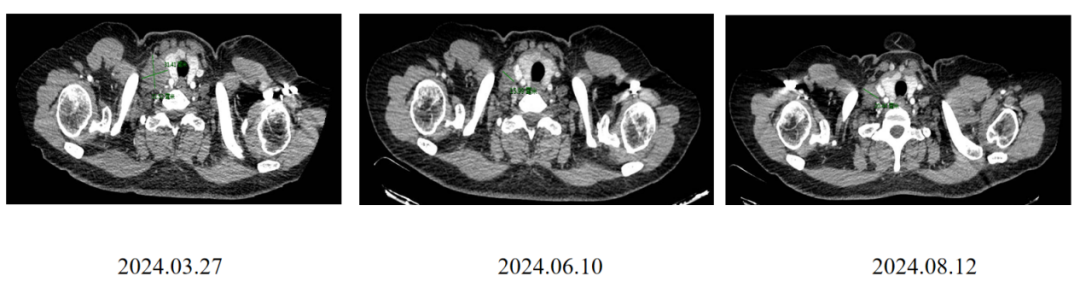

CT评估(右侧锁骨上区淋巴结):

CT评估(右胸壁):

二线治疗4周期后临床查体CR。

该病例为47岁的HER2+晚期乳腺癌患者,右乳癌术后辅助治疗(TCbH)3年后出现胸壁、区域淋巴结及骨转移。一线接受THP方案治疗约6个月后即出现局部进展,提示原发耐药。自2024年9月起,二线换用T-DXd进行治疗。疗效显著,治疗4周期后临床查体即达到CR,影像学评估显示病灶持续显著缩小。截至2025年9月异地就医前,患者持续处于“临近CR”状态,且安全性良好,未发生间质性肺病等严重不良反应。该病例成功印证了T-DXd对于THP治疗失败后的HER2阳性晚期乳腺癌患者,能够提供强效、深度且持久的疾病控制。